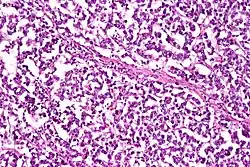

Dysgerminoma

Dysgerminomas are comparable to testicular seminomas and account for approximately 32- 37% of all OGCTs.[1] They are particularly prominent in individuals with dysgenic gonads of 46, XY pure gonadal dysgenesis patients.[1] Based on gross examinations, dysgerminomas are characterized by having a ‘solid, lobulated, tan, flesh-like gross appearance with a smooth surface'.[1] Microscopically, the cellular structure is distinguished by a round-ovoid shape containing ample eosinophilic cytoplasm and an irregularly shaped nuclei.[1] The uniformly positioned cells are separated through the fibrous strands and lymphocytic infiltration is commonly observed.[4]